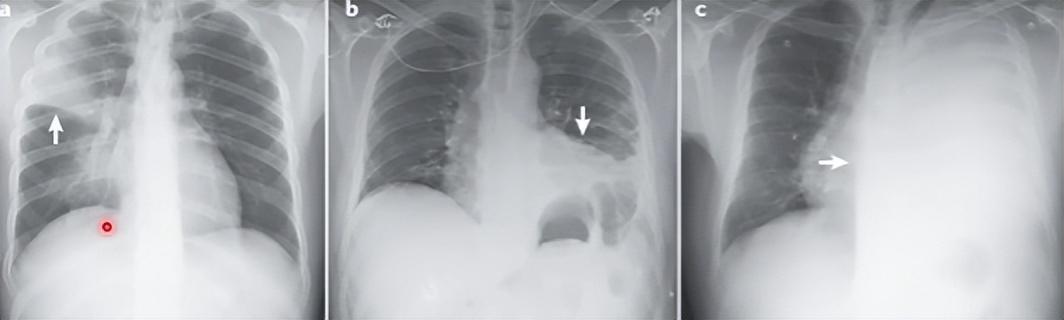

另外白肺也有轻有重

像左边这个“白肺”情况就相对轻,而右边的白肺就明显严重

较轻的白肺治疗康复都比较好,会慢慢恢复。

而表现重症的白肺,死亡率就较高了。